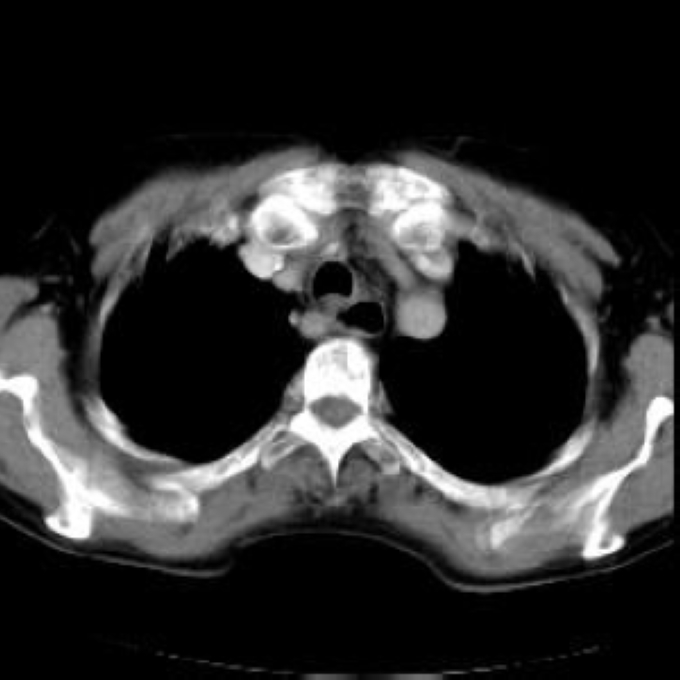

Arteria lusoria.

56 year old patient with dyspagia. A tumor of soft tissue was described in upper mediastinum on plain X-ray of the thorax. What is this mass in the upper mediastinum?